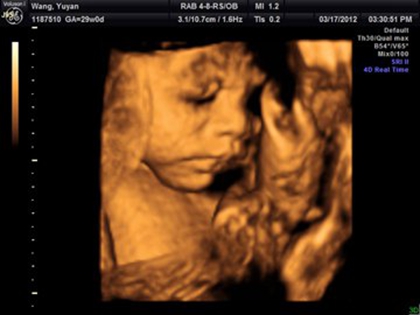

四维b超检查,确实需要宝宝配合,让宝宝动起来,通过四维b超动态的检测胎儿各个器官、皮肤与面部,所以很多网上的说法是女宝宝在做B超检查的时候更不容易配合,其实这种说法是没有依据的,宝宝在妈妈肚子里的时候会胎动,也会自己变换姿势,这是正常的,宝宝不配合和性别是没有关系的,如果做四维的时候想要让宝宝配合,那么就要想办法咯。

胎儿在4个月的时分就能够检测到性别了,但是精确率只要85%-90%,其中男宝宝的性器官比拟明显,精确率到达95%以上,而女宝宝的性器官并没有那么明显,精确率只要85%,当医生正在操作B超的时分,若宝宝正处于背部的姿态或手脚正好蜷到一同,从而遮挡了性别器官,这也会形成性别的改动,另外假如你家宝宝太调皮了,不太配合,姿态不对,医生也不可以很精确的看到Ta的生殖器,结果就没有那么精确了,所以四维还是有一定的概率会翻盘的。